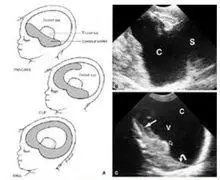

前脑无裂畸形全前脑分型

颅脑先天性疾病影像诊断_畸形